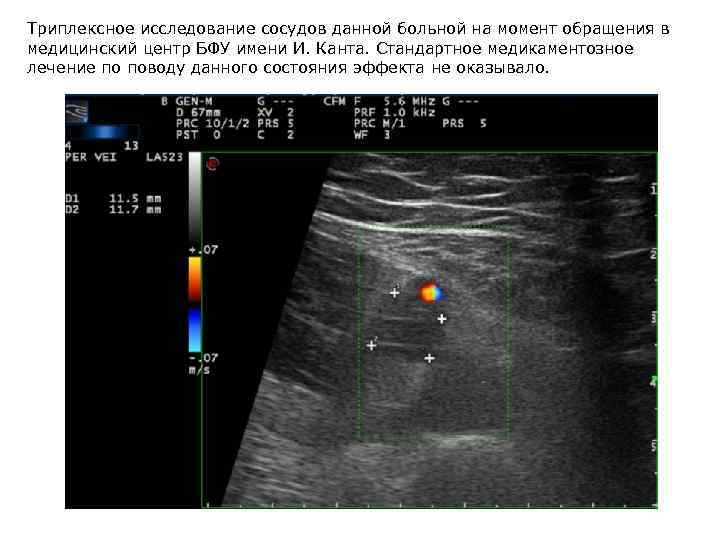

Женщина, 17 лет, беременность (III триместр). Тромбоз v. femoralis

Триплексное исследование сосудов данной больной на момент обращения в медицинский центр БФУ имени И. Канта. Стандартное медикаментозное лечение по поводу данного состояния эффекта не оказывало.

После анализа ГРВ был сделан вывод о значительных психоэмоциональных нарушениях у пациентки. При расспросе выяснилось, что у нее существовал длительный серьезный психологический конфликт с родственниками. Были даны психологические рекомендации, после нормализации отношений наступило значительное улучшение, по УЗИ отмечалось уменьшение размеров тромба и нормализация кровообращения в нижней конечности без назначения дополнительной терапии. По ГРВ в динамике отмечалось значительное улучшение (увеличилась общая площадь, повысилась однородность, исчезли дефекты энергетического поля). Впоследствии пациентка родила здорового ребенка. УЗ исследование плода данной пациентки